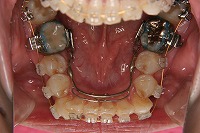

26歳4か月

下顎